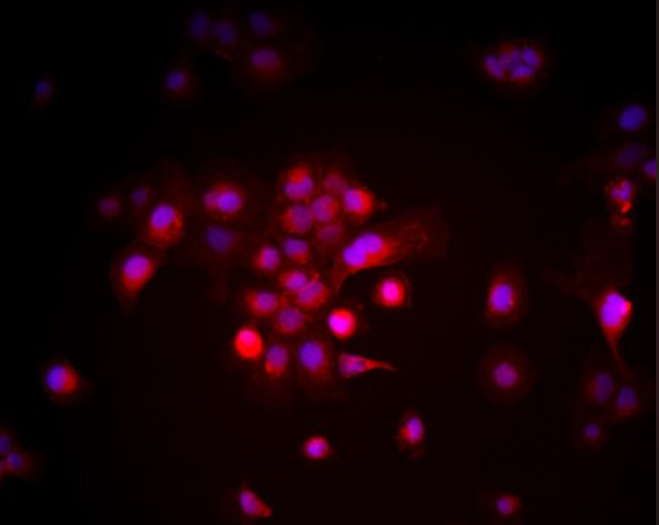

MOLM-13 人急性髓性白血病细胞 (Human Acute Myeloid Leukemia Cells, MOLM-13)

人急性髓性白血病(AML)患者外周血

人急性髓性白血病细胞系

悬浮生长

MOLM-13 人急性髓性白血病细胞(Human Acute Myeloid Leukemia Cells, MOLM-13)来源于一位急性髓性白血病(AML)患者外周血,是一株经典的AML研究细胞系。该细胞以悬浮方式生长,形态多为圆形或不规则形,具备高增殖能力。分子水平上,MOLM-13细胞携带MLL-AF9染色体易位[t(9;11)(p22;q23)],并常伴随FLT3-ITD突变,这些特征与临床AML的分子病理高度一致,因此在发病机制研究和靶向药物开发中具有重要应用价值。